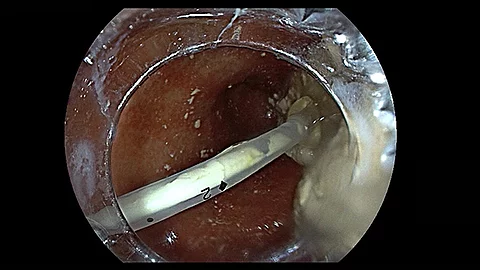

VideoEndoskopische Sichtkontrolle bei Ballondilatation

In unserem neuen Endoskopie-Video zeigt Ihnen PD Dr. Jochen Weigt, wie Sie während einer Ballondilatation – hier am Beispiel einer Pylorusdilatation – permanent die endoskopische Sichtkontrolle über den Dilatationsvorgang behalten können. Reinschauen lohnt sich!